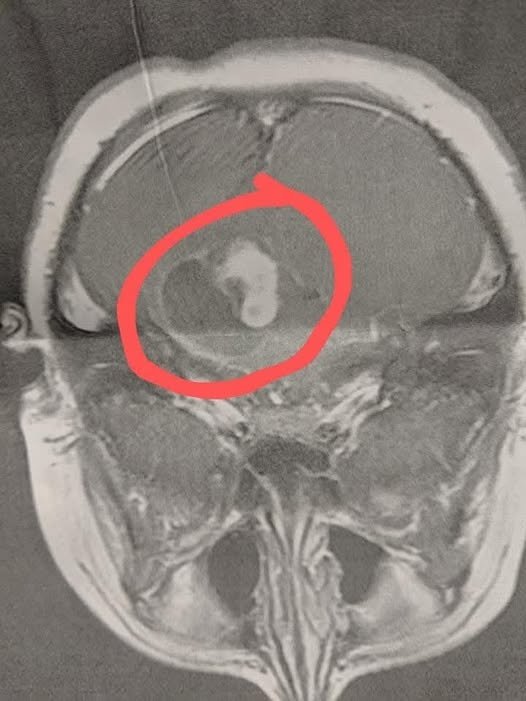

The doctor recommended we see an ENT. A few days later, the ENT told us that my son was completely deaf in his left ear and would need a cochlear implant. I asked him to slow down — I wasn’t ready to talk about an implant until we knew why my son suddenly lost hearing in one ear. The ENT didn’t seem to take me seriously, so I called our pediatrician and demanded an MRI. On New Year’s Eve 2020, we got a same-day MRI. On the way home, I got a call from the pediatrician telling me to come in immediately for the results. In that moment, I knew something was very wrong. The MRI showed a large brain tumor with fluid around it.

My son had emergency surgery at Duke that same day. The operation lasted 8 hours. The surgeon was able to remove 90% of the tumor, but the remaining 10% was on his brain stem and too dangerous to remove. Six weeks later, we did a follow-up MRI to see how things were healing, and we received devastating news — the tumor had grown back. My son started chemotherapy right away and went through a full year of intense treatment. Today, he has been stable for 3 years. I share this story in the hope it helps someone else. Take your children to their yearly checkups, even if they seem perfectly healthy. That physical, our pediatrician, and the neurosurgeons saved my son’s life. His next routine MRI is coming up next month, and we are hoping it shows the tumor is still stable. ” title